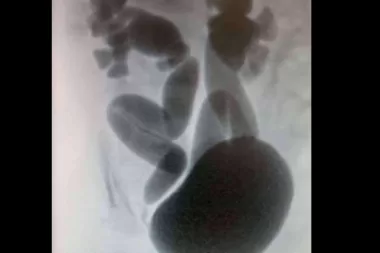

Reflujo vesicoureteral en niños. Diagnóstico y tratamiento por el Dr. Daniel Cabezalí

Remitido